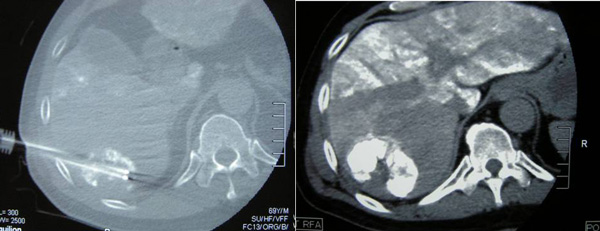

TACE was continued and on 16 September 2010, radiofrequency ablation (RFA) of the liver tumour was performed using a 2.5 x 20 cm cluster Cool-Tip RF electrode system. Two cycles of ablation were performed with repositioning of the cluster electrode in-between each cycle.

CT scan on 6 October 2010 showed the tumour was significantly smaller in size, 4.7 x 5.4 x 4.6 cm. There was no evidence of recurrent or new lesions in the rest of the liver. No evidence of pulmonary metastataic deposits and no enlarged mediastinal or lymph nodes.

On 6 April 2011, a CT scan was performed. The previously treated mass in the right lobe of his liver measures approximately 3.5 x 5.1 x 4.8 cm in size. There is no associated hypervascularity seen with this mass. However, there is a new lesion in segment 5 of the right lobe of his liver. It is 3.1 x 2.3 x 3.6 in size.  This mass was not present on the previous scan of October 2010 and is suspicious of recurrent disease.

TD came to a private hospital in Penang and underwent a CT scan of his brain, neck, thorax, abdomen and pelvis on 12 August 2011. The results showed:

1. There is a 5.1 x 4.2 x 4.8 cm mass in segment 6 of the liver.

2. There is a 2.7 x 2.8 x 3.3 cm enhancing lesion in segment 5 of the liver.

3. There is an ill-defined enhancing lesion measuring about 2.3 cm in segment 8 of the liver.

4. There is a 2.5 x 2 x 2.1 cm mass just inferior to the right adrenal gland. Metastasis?

5. There is a 1.9 x 1.6 x 2.5 cm mass just inferior to the left adrenal gland. Metastasis?

6. There is a lytic lesion in the vertebral body of T12. Fracture of the superior endplate of T12 is noted. This probably represents a bony metastasis.